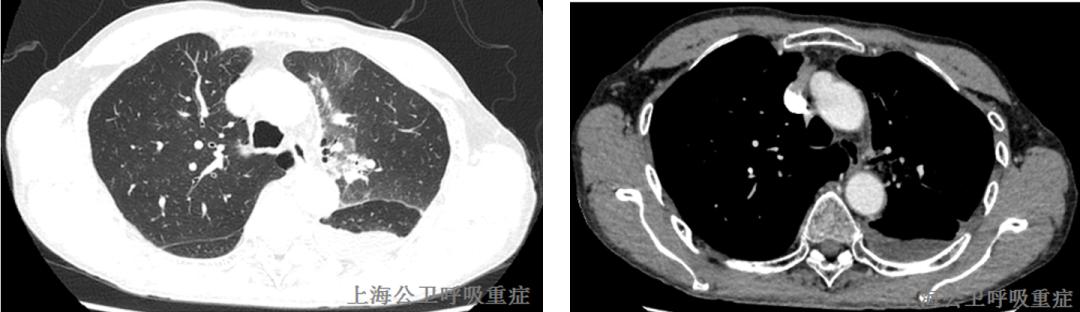

2020.10.22胸部CT增强示:左上肺尖后段、左上肺前段、左下肺前基底段及外基底段实性结节,左肺散在炎症,左侧胸膜局灶性增厚,左侧胸腔少量积液,左下肺部分膨胀不全;MT待排,请结合临床并进一步检查。左侧肺门淋巴结肿大。两上肺胸膜下小肺大泡。

2020.11.30复查胸部CT示:左肺上叶尖后段、左肺下叶外基底段及前内基底段实性结节;左肺少许炎症;左侧少量胸腔积液;左侧胸膜增厚;较前2020-11-26片,左肺下叶前内基底段病灶略减小,左肺下叶外基底段新发实性结节,左侧胸腔积液略增多,左肺上叶尖后段病灶相仿。左肺门淋巴结肿大,与前片相仿;两上肺胸膜下小肺大泡。气管右后方增厚软组织影,建议颈部MRI增强检查。